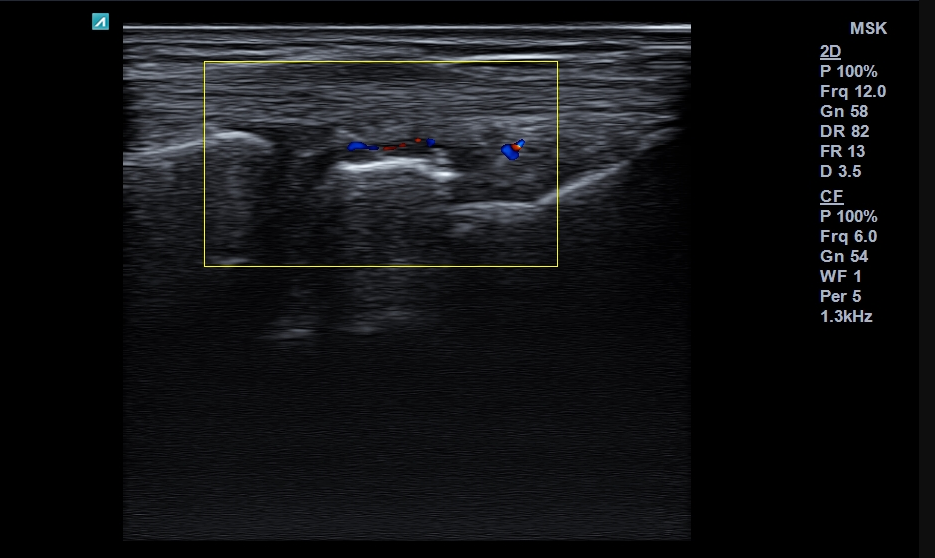

Musculoskeletal ultrasound is a non-invasive diagnostic method used to visualize soft tissues around the joints, as well as the bony structures. It is a painless, fast, and cost-effective imaging technique. The examination can be repeated as often as necessary without exposing the patient to radiation.

In many cases, ultrasound can serve as an alternative to MRI, saving the patient time and money, while complementing the overall assessment of joint conditions. Ultrasound is also used in suspected temporal arteritis, helping to confirm or exclude the diagnosis

With the help of ultrasound, we can detect:

- Tendonitis and tenosynovitis (inflammation of tendons and their sheaths)

- Tendinopathy

- Joint effusion (fluid in the joint)

- Calcifications

Ultrasound can also be used as guidance during intra-articular injections.